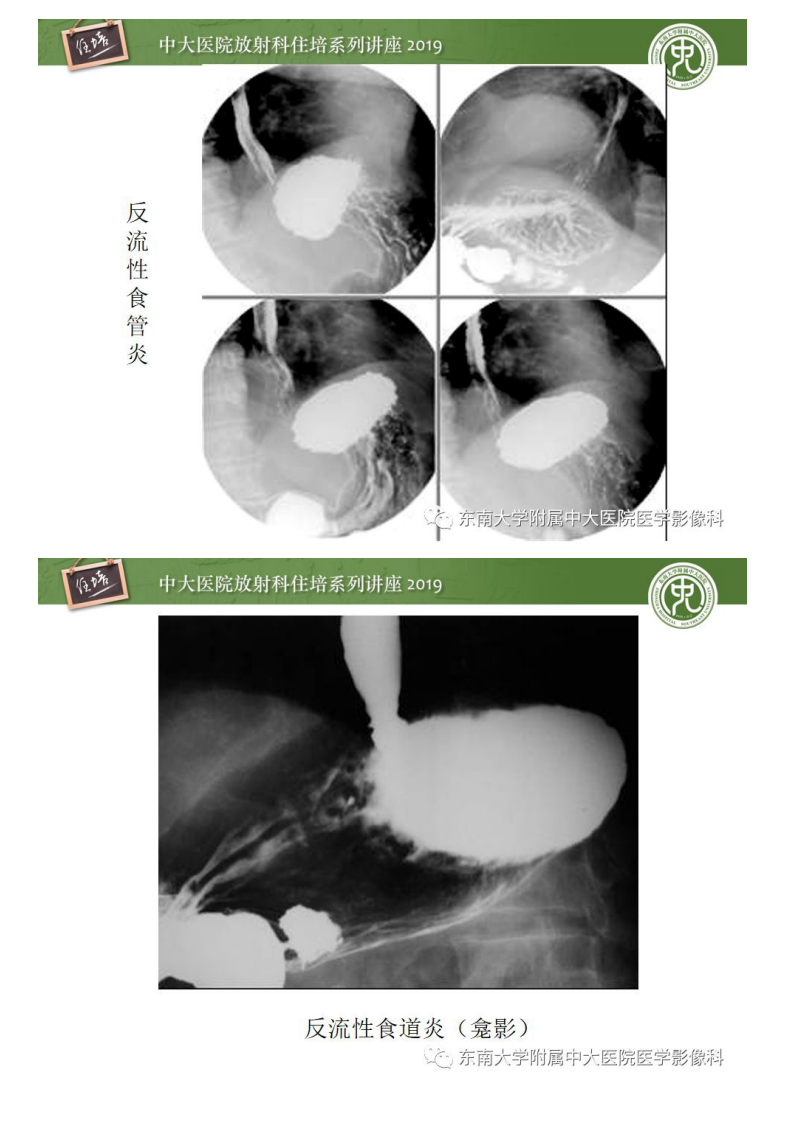

20200220_1【中大放射住培系列讲座】食管常见疾病的诊断和鉴别诊断.pdf